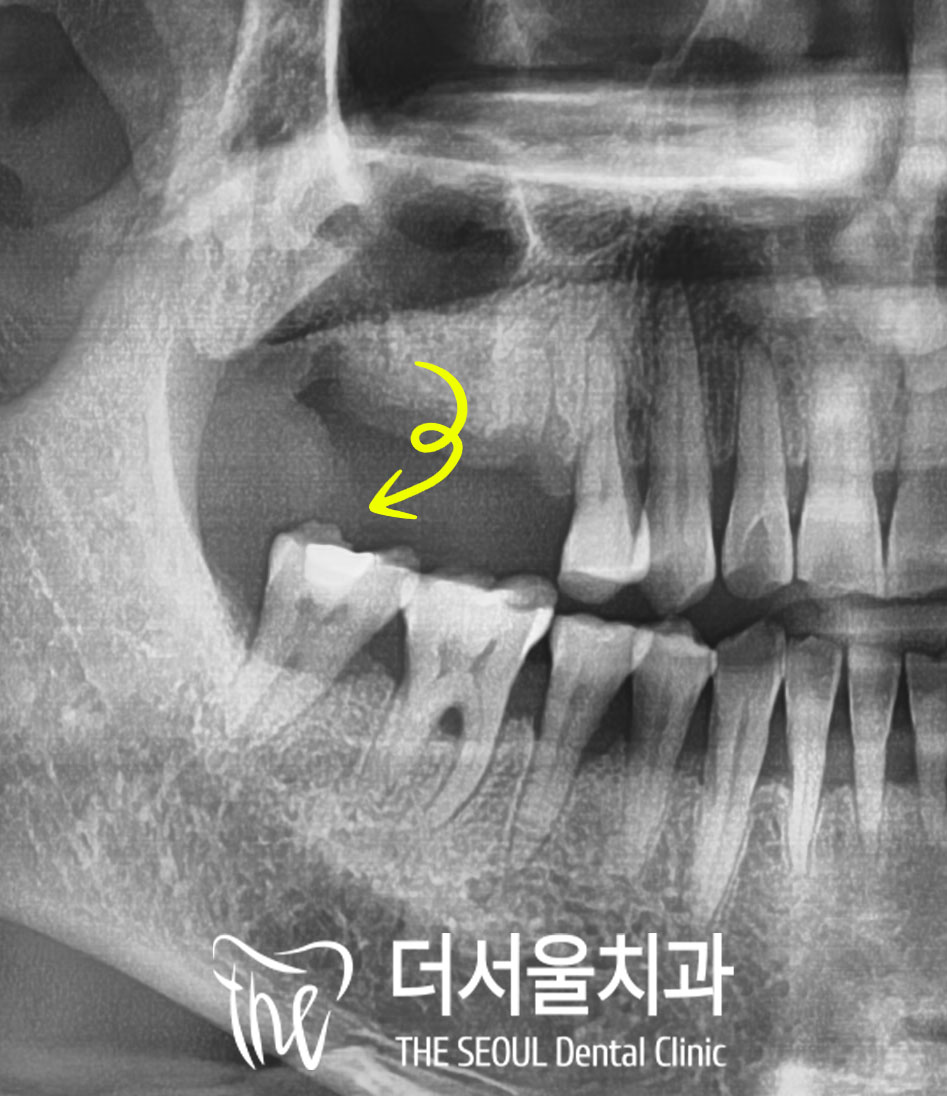

구강을 살펴보면

오른쪽 위 첫번째 큰 어금니가 빠져있고

그 주변 치아도 심한 우식이 생겨

상태가 좋지 않습니다.

또한 교합면에서 촬영한 사진이라

잘 보이지는 않으나

그 앞에 있는 작은 어금니도

잇몸뼈가 내려가고

치주염이 심했습니다.

검진을 할 때도

동요도가 매우 커서

금방이라도 빠져버릴 것만 같았습니다.

3. 디지털 네비게이션 가이드

이 케이스에서 수술할 부위는

앞서 말씀드린 것처럼

상악동이 있는 어금니 위턱뼈입니다.

그래서 수진동 임플란트 시술 전

디지털 방식을 이용하여

남은 잔존골의 양이 부족하다 보니

이대로는 픽스처를 심을

충분한 길이가 확보되지 않아

상악동을 들어 올리는 거상술을

동시에 진행하기로 했습니다.